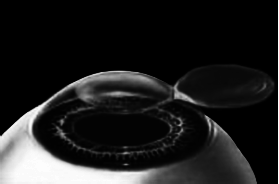

Итак, головка присоединяется к вакуумному кольцу и по специальным полозьям двигается над куполом роговицы (рис. 3). Срез, или отслаивание (называйте, как хотите), проводится не полностью, у крышечки (роговичного лоскута) остается маленький участок на периферии, соединяющий ее с роговицей (рис. 4).

Рис. 4. Роговичный лоскут сформирован.

Иллюстрация с сайта Международного лазерного центра www.optics.ru